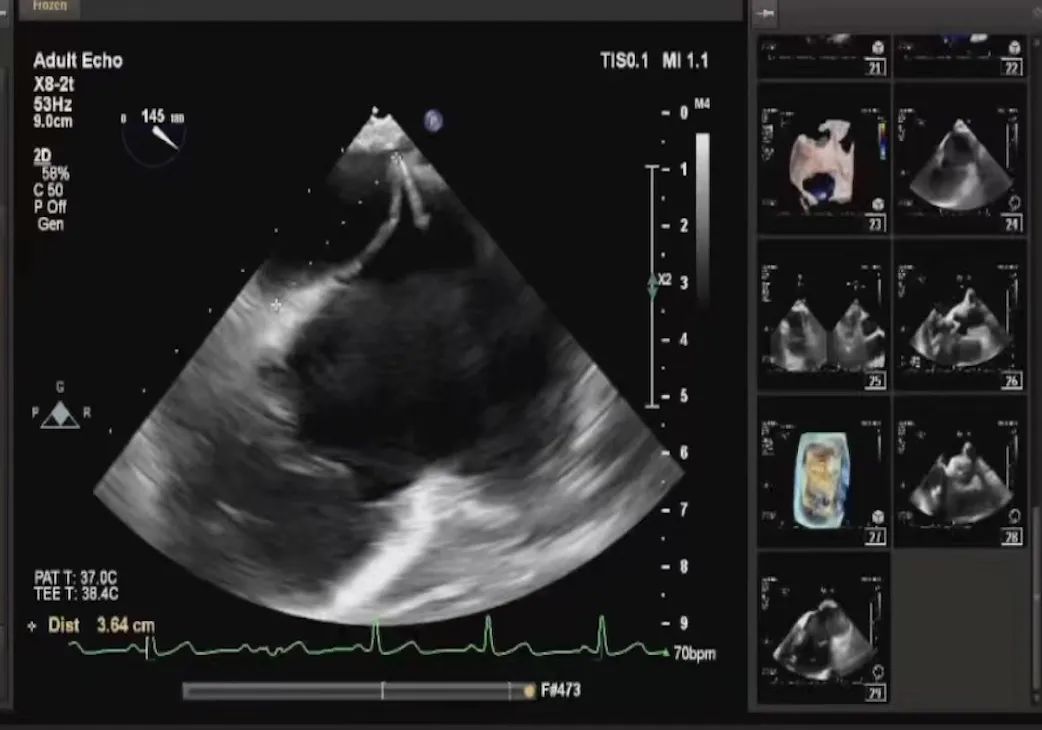

患者全身麻醉消毒铺巾后,建立右侧股静脉入路,在经食道超声指导下房间隔穿刺。根据要求,房间隔穿刺高度至少需要4.0cm,患者本身的解剖结构,左房和右房都比较小,如果选取卵圆窝靠后,靠中上的位置穿刺点高度只有2.6cm,是无法完成整个手术操作的,那么想要在安全的前提下获得更充分的房间隔穿刺高度,考虑选择在房间隔肌部穿刺,采用穿刺针的内芯,PCI导丝,甚至电刀穿刺的方式,都无法突破房间隔。患者的卵圆窝松弛,肌部又硬,苏晞院长团队决定在肌部与膜部交界的位置穿刺,经过精细调整,精准定位,最终以3.64cm的极限高度突破房间隔,而后将MitraClip™可操控导引导管(SGC)送入左心房。

将MitraClip™XTR送入左房,由于左房太小,在达到骑跨过程中反复推进回撤CDS和稳定器,同时旋转SGC,达到骑跨的同时,保证Clip头端游离,且SGC在左房有深度。旋转M,同时顺时针往后旋转SGC借高度,使Clip垂直二尖瓣环平面,由于穿刺高度不够,Clip直接进入左室,这意味着操作要十分小心,左室组织复杂,稍有不慎将会造成组织损伤。使用A/P Konb中“A”旋钮借高度。确认垂直后,直接在左室打开Clip,3D外科视角,逆时针旋转使Clip夹臂处于11点-5点方向,回拉稳定器,使Clip处于3区脱垂区域,用“+/-”Knob中的“-”旋钮,使Clip更往后叶的同时增加操作高度,抓捕脱垂的瓣叶,关紧Clip后,反流从4+降低至0级,平均跨瓣压差2mmHg,左右肺静脉逆流均改善。前后叶活动度降低,后叶插入长度9mm,前叶插入12mm, 确认稳定性后释放Clip。释放后,即刻效果十分满意,手术圆满结束。